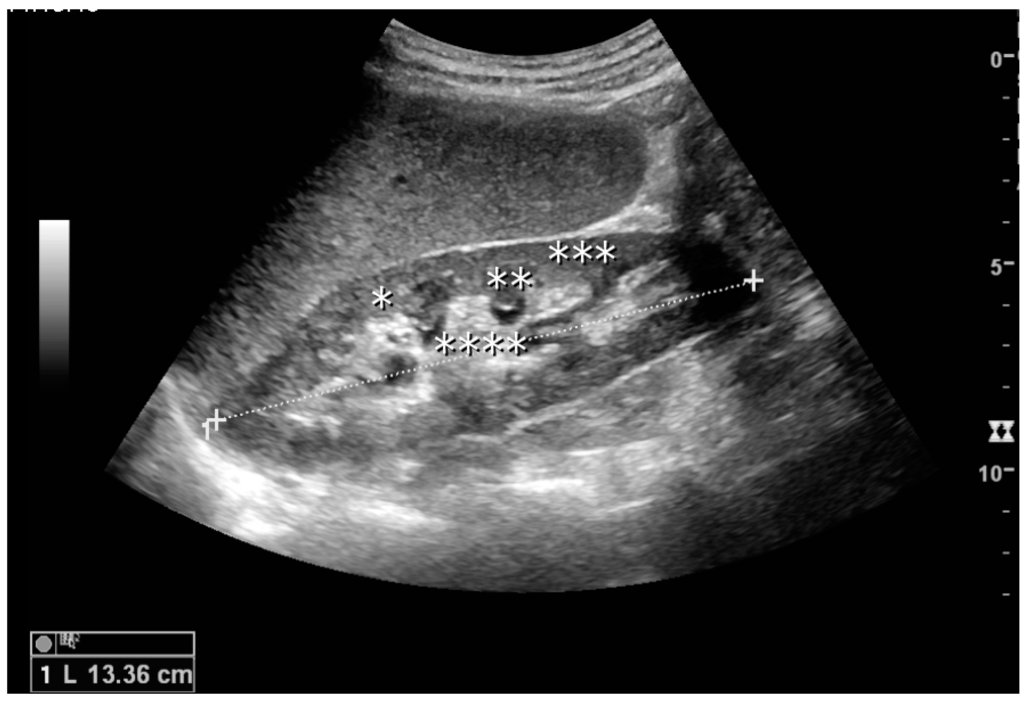

The kidney is divided into parenchyma and renal sinus. The renal sinus is hyperechoic and is composed of calyces, the renal pelvis, fat and the major intrarenal vessels. In the normal kidney, the urinary collecting system in the renal sinus is not visible, but it creates a heteroechoic appearance with the interposed fat and vessels. The parenchyma is more hypoechoic and homogenous and is divided into the outermost cortex and the innermost and slightly less echogenic medullary pyramids [3]. Between the pyramids are the cortical infoldings, called columns of Bertin (Figure 1). In the pediatric patient, it is easier to differentiate the hypoechoic medullar pyramids from the more echogenic peripheral zone of the cortex in the parenchyma rim, as well as the columns of Bertin (Figure 2) [2,4].

Figure 1. Normal adult kidney. Measurement of kidney length on the US image is illustrated by ‘+’ and a dashed line. * Column of Bertin; ** pyramid; *** cortex; **** sinus.